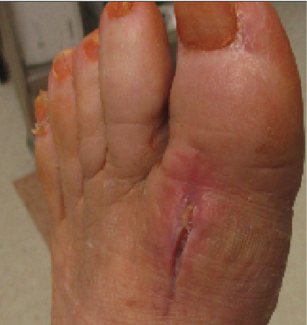

The author presents a case report on a non-diabetic male with osteomyelitis after an arthrodesis procedure. With an absorbable antibiotic cement spacer, surgeons salvaged the first ray, which is crucial in preventing subsequent foot and ankle...